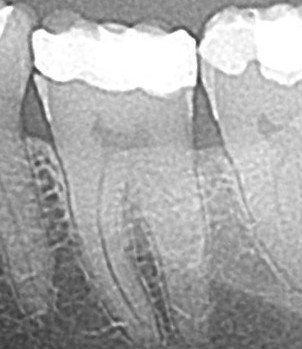

Simptomi koji upućuju da je na zubu potrebna endodontska terapija su

jaka bol u širem području oko određenog zuba,pulzirajuća bol,iznenadna

oteklina područja oko tog zuba a ponekad nema nikakvih simptoma

osim postojećeg periapikalnog procesa(granuloma) na RTG snimci.